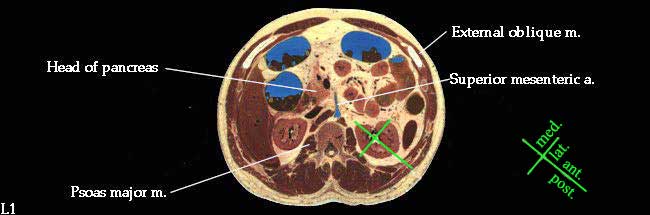

1. Demonstrate the relationships of the kidneys and suprarenal glands to adipose and fascial coverings, lower ribs and other abdominal organs. (W&B 489-493, N 273,329,330,354 or TG 5-30, 5-31, 5-42)2. Describe the basic internal gross anatomy of the kidney. (W&B 491-493, N 334A, 334B or TG 5-32A, 5-32B).The orientation of the kidneys is best illustrated with a cross-section.

Since they lie against the psoas muscle (which lies against the vertebral column), their posterior surfaces are somewhat medial as well, while their anterior surfaces are also lateral. The convex lateral border (the outside of the "bean") is also posterior, and the medial border, with the hilum, is also anterior.